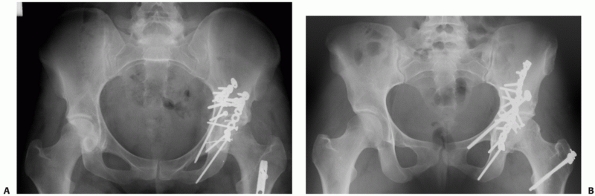

FIGURE 45-1 A.

Anteroposterior (AP) radiograph in traction of a 42-year-old man at the time of transfer to our center, 3 weeks after sustaining a displaced transverse right acetabular fracture in a motor vehicle accident. Subsequently, open reduction and internal fixation was performed. B. AP radiograph at his 20-year follow-up examination. The patient had returned to full activities within 1 year of his accident and continued to be asymptomatic regarding the right hip. (Copyright Berton R. Moed, MD.) |